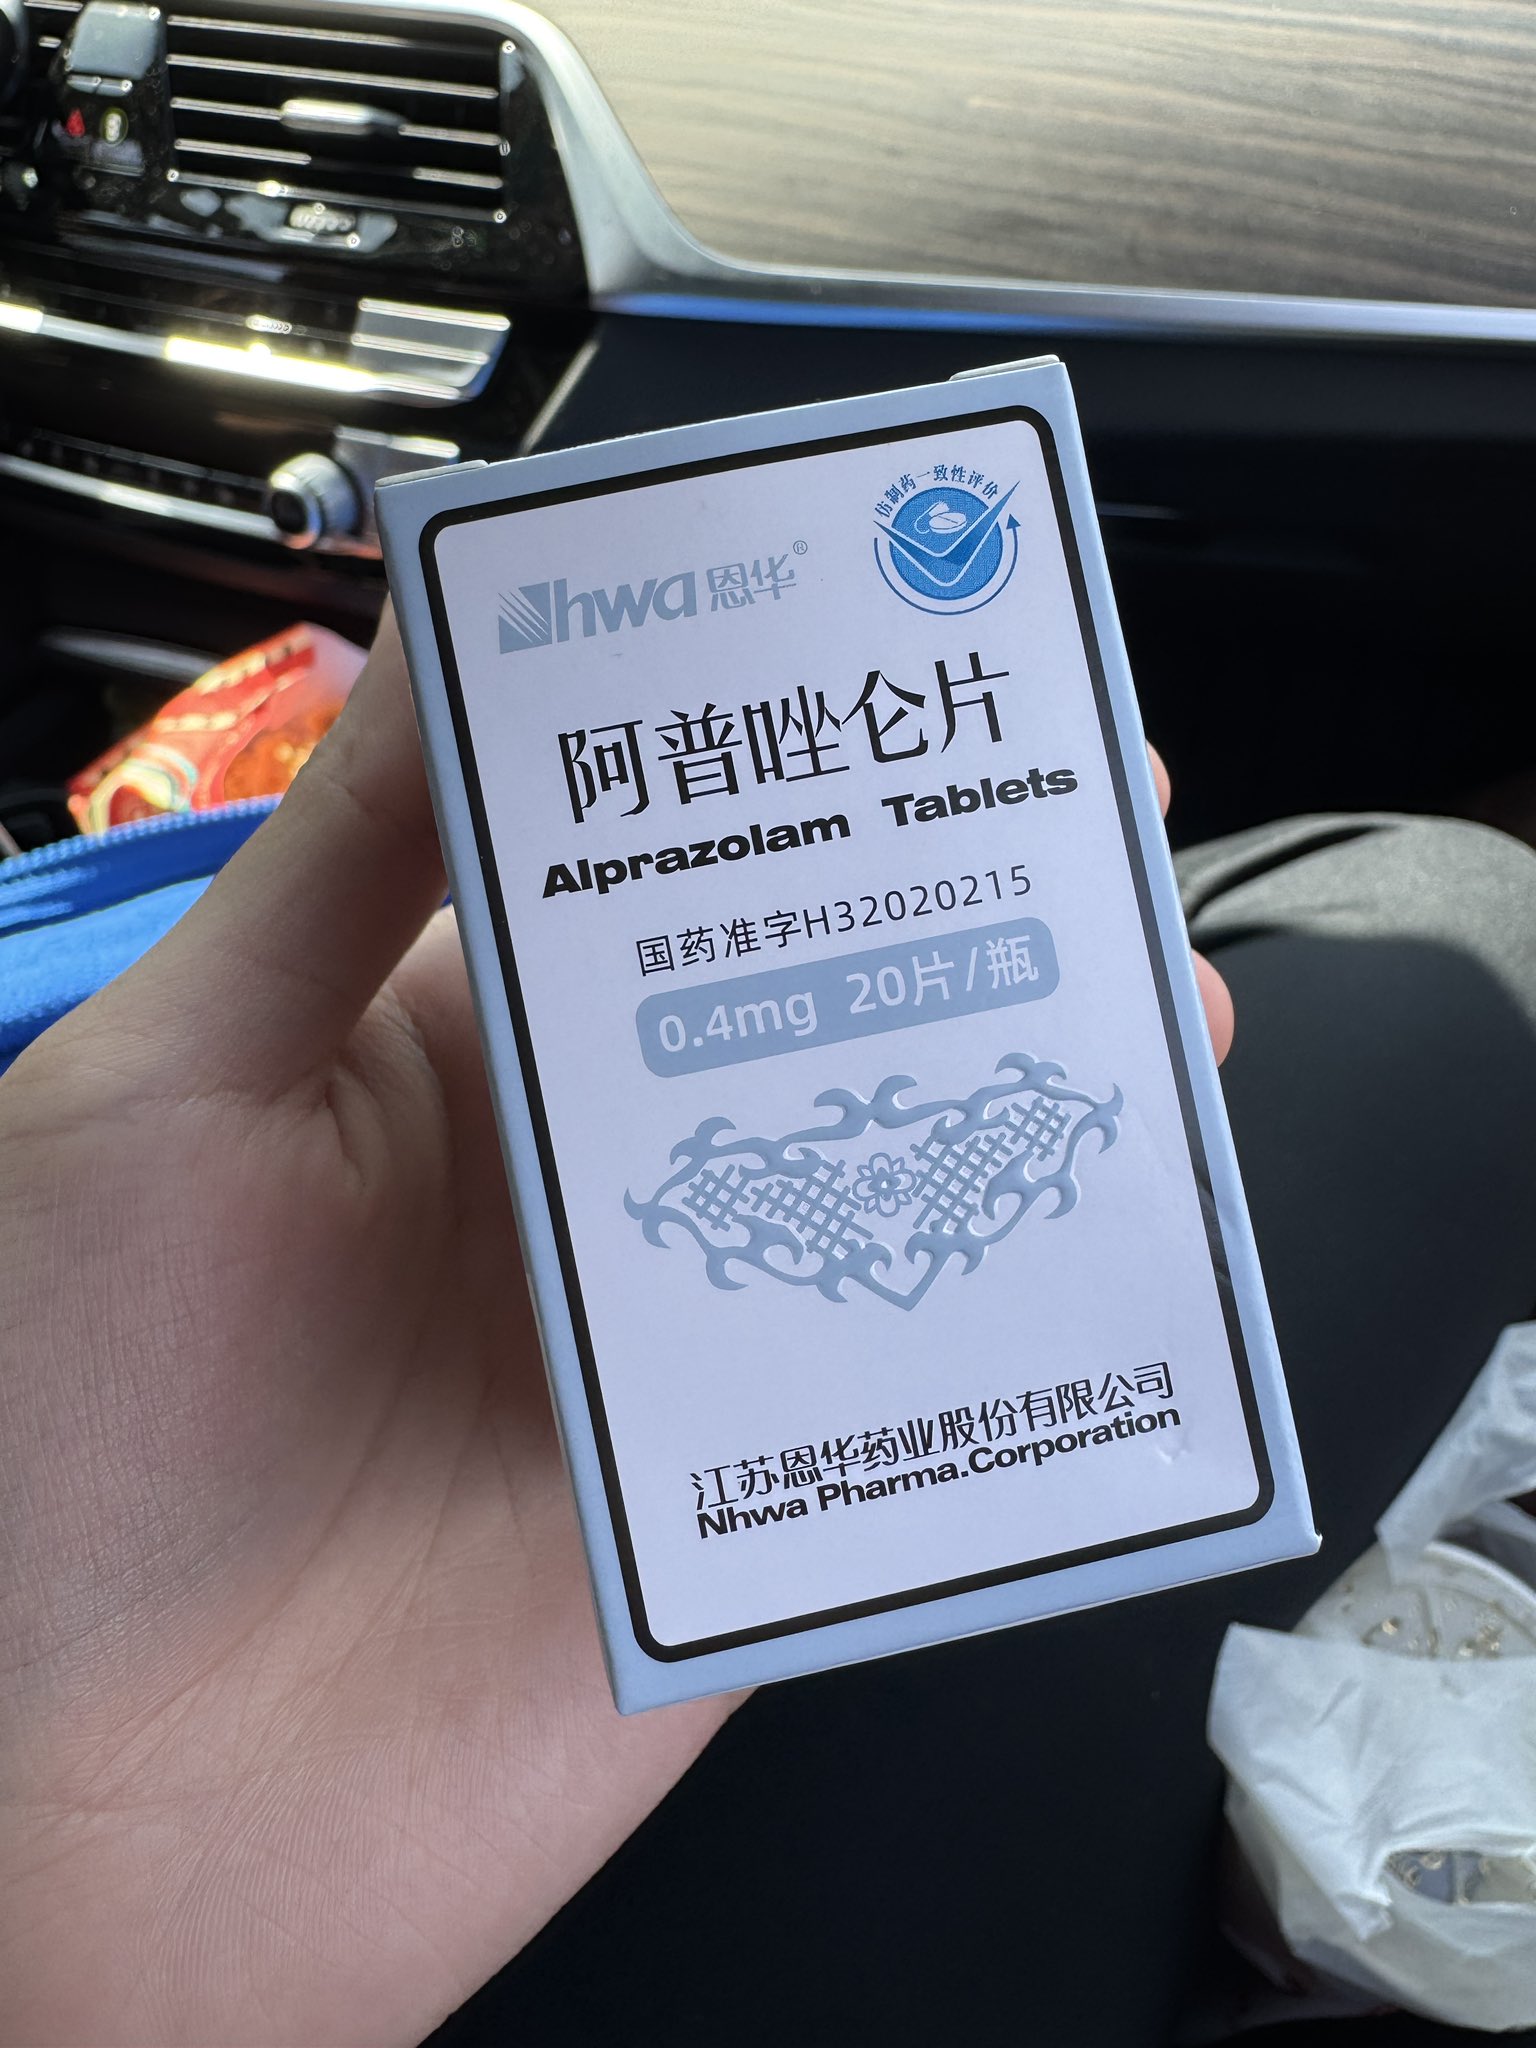

炽烈已极 @AnIncandescence苯二氮卓类药物:镇静作用。bzd通过提高内源性化学物质GABA的有效性来降低神经元的兴奋性。 https://t.co/Z1mc5JJGrg

炽烈已极 @AnIncandescence已知阿普唑仑对伴有恶心呕吐症状的过量有额外作用,它本身有联用其他药物治疗化疗引起的恶心的用途。